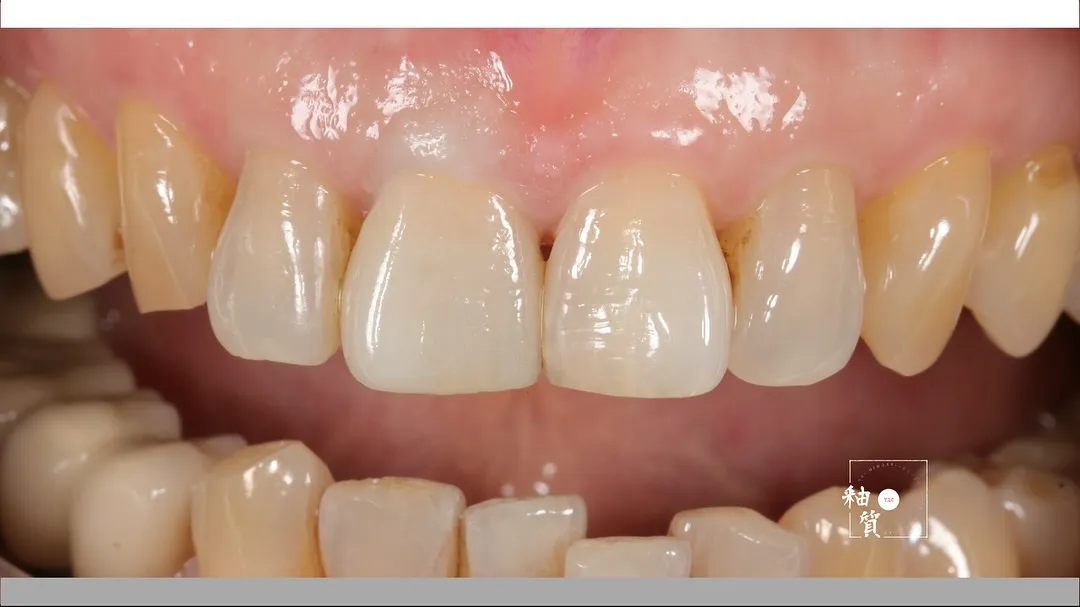

12 x 21 - 唇側燒瓷

12 x 21

唇側燒瓷

唇側燒瓷